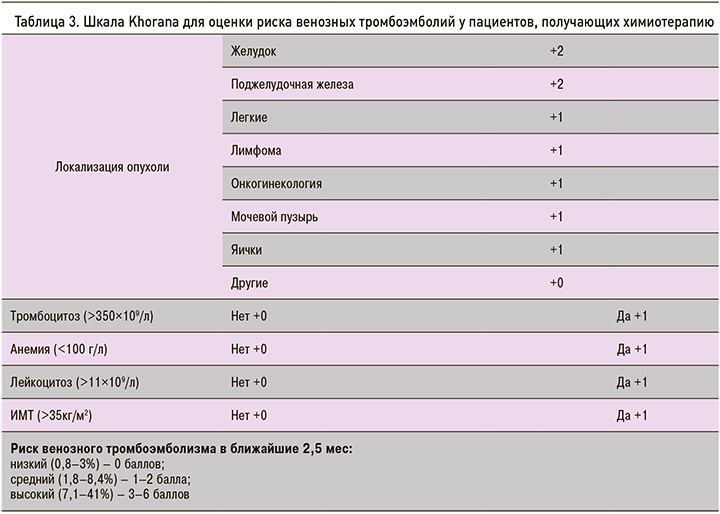

Для определения рисков ВТЭ у онкологических больных используются различные шкалы. Американское общество клинической онкологии (ASCO) в настоящее время рекомендует использование шкалы Khorana (табл. 3) для определения риска развития ВТЭ до начала проведения химиотерапии и периодически после окончания ее [19–21].

Позже эта модель была дополнена внедрением двух дополнительных биомаркеров – D-димера и растворимого P-селектина, показавших высокую прогностическую ценность (шкала Vienna CAT) [19]. В представленном случае у пациента риск развития ВТЭ был оценен как высокий (4 балла).